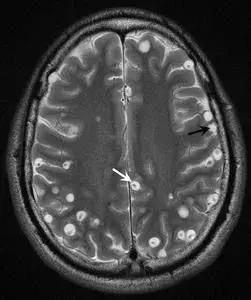

去年二月,有一个网友结婚到大理洱海蜜月旅行,他们点了一盘酱爆田螺,吃完之后就开始头痛恶心,发烧呕吐,去了好几家医院查都查不出个所以然来。最后才发现,原来是寄生虫入侵脑部引起颅内感染。

后来,她才知道她吃的那个不是田螺,而是福寿螺。她感染了广州管圆线虫,这种寄生虫,首先侵袭肺部,随后随血液进入脑部,打洞做窝。

她一直没在意,等到一次突发癫痫病,送到医院才发现,寄生虫甚至已经到她的大脑里打洞做窝了,可惜发现得太晚,女孩没过多久就去世了。

父母不甘心,要求做尸检。男孩全身都是正常的,直到打开颅腔,法医才发现了满脑的虫子!而这些虫子,不是蛔虫,而是猪肉绦虫的囊尾蚴。

到了脑组织发育产卵后,会压迫脑组织,引起组织炎症,危及生命。